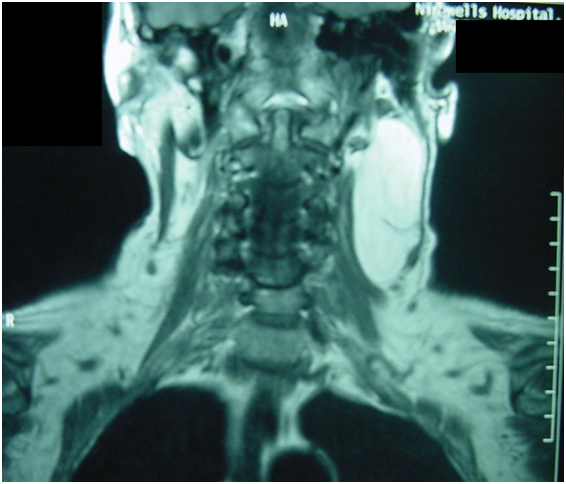

A 68-year old Caucasian female presented to the Otolaryngology clinic for evaluation of hoarseness. Fibreoptic laryngoscopy revealed partial left vocal cord palsy. A lobulated cystic mass in the left side of the neck was noted on neck palpation. The patient reported this to be asymptomatic and to have been present from infancy with gradual enlargement. A chest radiograph was normal. Computed tomography of the neck and thorax demonstrated a large radiolucent mass in the left neck consistent with the diagnosis of a lipoma. This extended from the mastoid tip cranially to the body of the fourth cervical vertebra caudally (Figure 1). No laryngeal or intrathoracic abnormality was found and the vocal cord palsy was considered to be idiopathic. Further examination after a course of voice therapy confirmed normal symmetrical vocal cord movement with restoration of voice.

Figure 1 Computed tomography (axial cut) appearance at initial presentation.

A CT scan with contrast at initial presentation showed a low-attenuation mass with Hounsfield units of - 43.0 in the left side of the neck extending from the skull base to the level of the fourth cervical vertebra. The characteristic CT appearance of lipoma is that of low attenuation related to fatty tissue (Hounsfield values –50 to –150). The MRI appearance was of a mass with a high-intensity signal on T1-weighted images and an intermediate signal on T2-weighted sequences. The appearance of lipomas on CT and MRI has been considered diagnostic, although neither of these imaging techniques can distinguish a lipoma from a liposarcoma.8 An irregular radiographic interface between lipoma and muscle tissue has previously been predictive of infiltration histologically.9